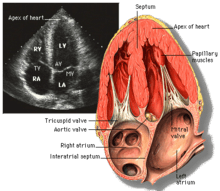

Echocardiogram

Transthoracic echocardiogram uses ultrasonic waves for continuous heart chamber and blood movement visualization. In recent times, it has become one of the most commonly used tools in diagnosis of heart problems, as it allows non-invasive visualization of the heart and the blood flow through the heart, using a technique known as Doppler.